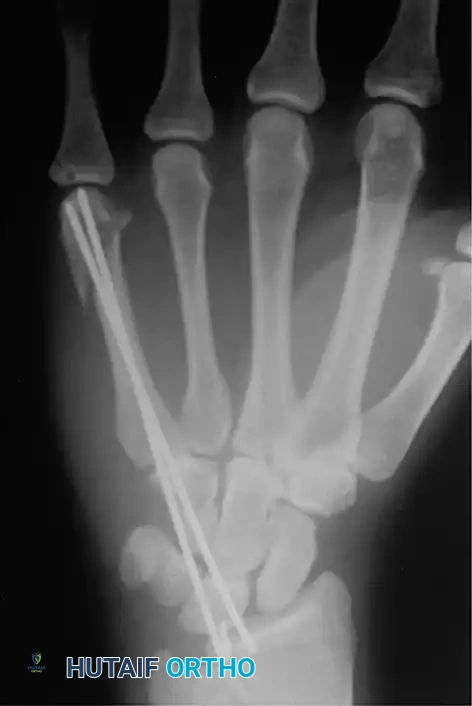

Fig. 64-37 Radiograph showing reduction and fi xation of fracture of metacarpal shaft and neck.

Alternatively, closed percutaneous pinning can be performed. With the MCP joint acutely flexed (to tighten the collateral ligaments and control the distal fragment), introduce a K-wire through the metacarpal head and advance it across the fracture site under fluoroscopic guidance.